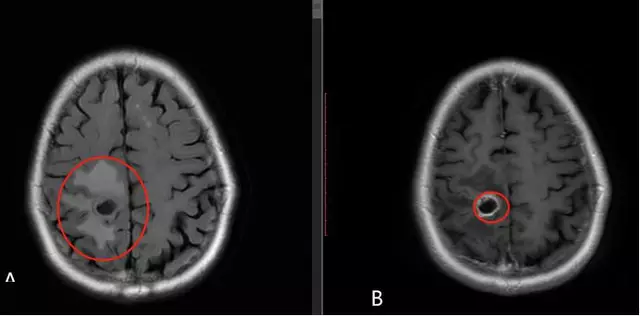

![]()

大脑半球受累常表现为一侧运动、感觉障碍及失语等,脑干受累常见表现为复视、头晕、构音不清、吞咽困难、走路不稳,神经系统检查示眼球外展受限、眼球震颤、面神经瘫痪、舌肌萎缩、咽反射消失、肢体共济失调等脑桥及延髓受损征象,严重者出现呼吸肌麻痹、心跳骤停,导致死亡。